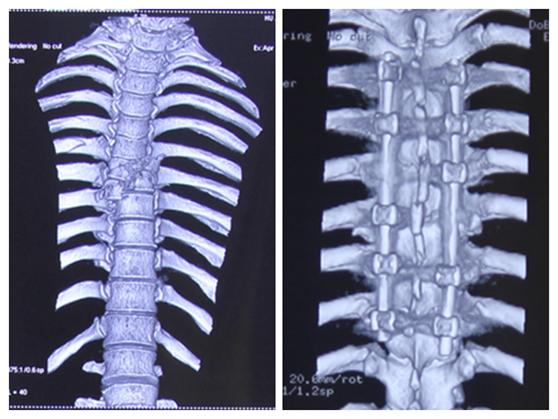

入院后,唐都医院神经外科给予高度重视,积极行术前检查。神经外科脊柱脊髓疾病治疗组组长李维新教授*析王分**先生影像学检查资料,指出“从患者影像学资料来看,1.胸6、7椎体骨折,脊髓轻度受压;2.胸6、7椎体爆裂性骨折,颈7椎体棘突骨折,左侧1、2肋骨及右侧第6肋骨骨折。”

影像学资料

手术前后对比